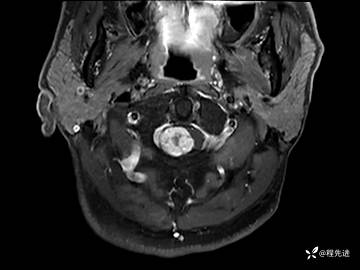

MRI平扫+增强:

T2压脂:

T1增强: